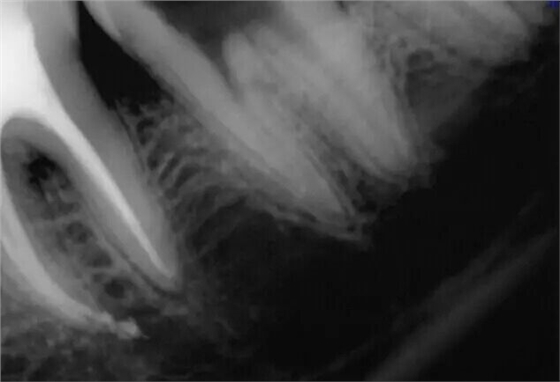

震出一半時照的X片

取出斷針時的X片